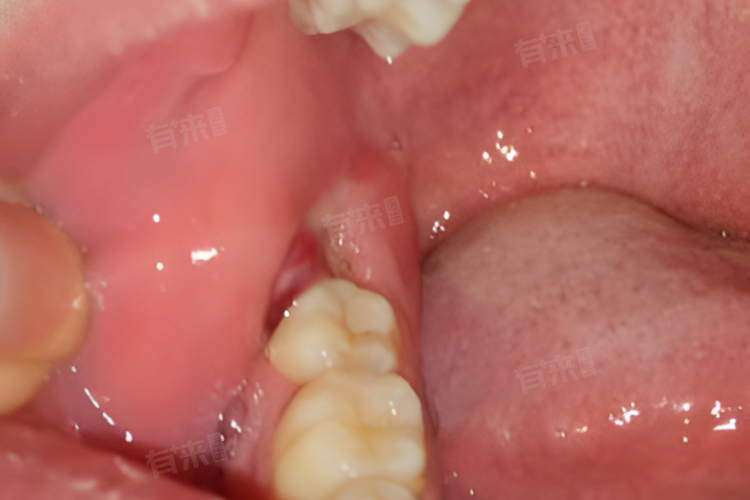

智齿萌出前,其对应的牙龈部位可能会出现轻微的肿胀,用手触摸能感觉到牙龈比周围正常牙龈要饱满、隆起一些,看起来也会比平常更红,而且这种肿胀感可能是持续性的,虽然初期肿胀程度不太明显,但随着智齿逐渐往外生长,肿胀会越发明显,有时候还可能伴有轻微的压痛,让人感觉牙龈处有点 “胀胀的” 不舒服。

部分人会感觉到智齿萌出部位的牙龈有瘙痒感,就好像有东西在牙龈里面轻轻挠一样,总是忍不住想用舌头去舔舐或者用手去触碰,试图缓解这种瘙痒的感觉,这其实是智齿在牙槽骨内顶破牙龈往外生长过程中,对牙龈组织产生刺激所引发的一种异样感觉。

智齿萌出过程中,会时不时地出现轻微的疼痛,多为隐痛、钝痛,疼痛程度不太强烈,一般不会对日常生活产生太大影响,但会间断性地发作,比如在咀嚼较硬食物、张大嘴巴、长时间说话等口腔活动较多的时候,疼痛可能就会出现或者加重。

有时候还可能影响到相邻的牙齿,使邻牙出现轻微的酸痛、胀痛感,这是因为智齿萌出的位置和方向如果不正,可能会对邻牙施加额外的压力,导致邻牙受力异常,出现短暂的疼痛不适,不过这种邻牙的疼痛相对也比较轻微,容易被忽视。

感觉口腔里好像多了个东西,尤其是在后牙区,会察觉到有隐隐的异物存在,即使看不到智齿已经萌出,也能凭感觉知道那个区域和平时不太一样了,在吞咽口水或者做咀嚼、咬合动作时,这种异物感可能会更加明显。